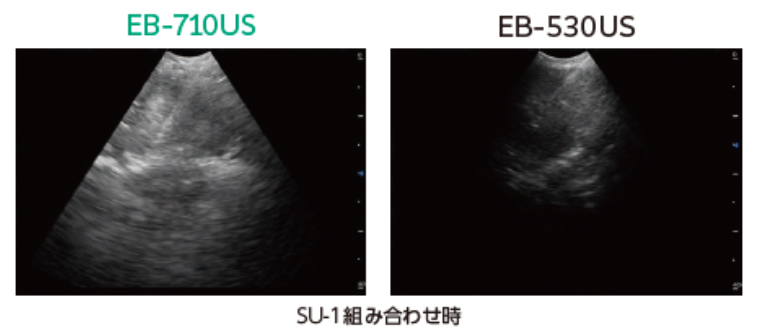

今回発売する「EB-710US」は、バルーンを装着せずに超音波観察が可能になりました。従来機*2より先端部径を6.7mmから6.4mmと0.3mm細径化し、先端部も約3?短縮。最大湾曲角度は180°に拡大し、針を挿入した状態でもスコープの大きな湾曲を維持することを実現したことで、スコープの挿入性とリンパ節へのアプローチ性の向上が期待できます。さらに、バルーンレスによる検査準備の簡略化により、ワークフローの効率化にも貢献します。

*2 当社従来機種「EB-530US」との比較。

当社従来機種と比較して先端部径を6.7mmから6.4mmと0.3mm細くしながら鉗子口径は0.2mm大きくしました。また、最大湾曲角度は180°に大きくし、針を挿入した状態でもスコープの大きな湾曲を維持することが可能です。これらにより、従来アプローチが困難であった縦隔リンパ節や肺門リンパ節へのアクセス性を向上させ、バルーンを装着せずに十分な超音波観察ができることを目指しました。

(2)小型で高性能な超音波振動子の搭載

分解能と深達度の向上により、鮮明な超音波画像が得られます。